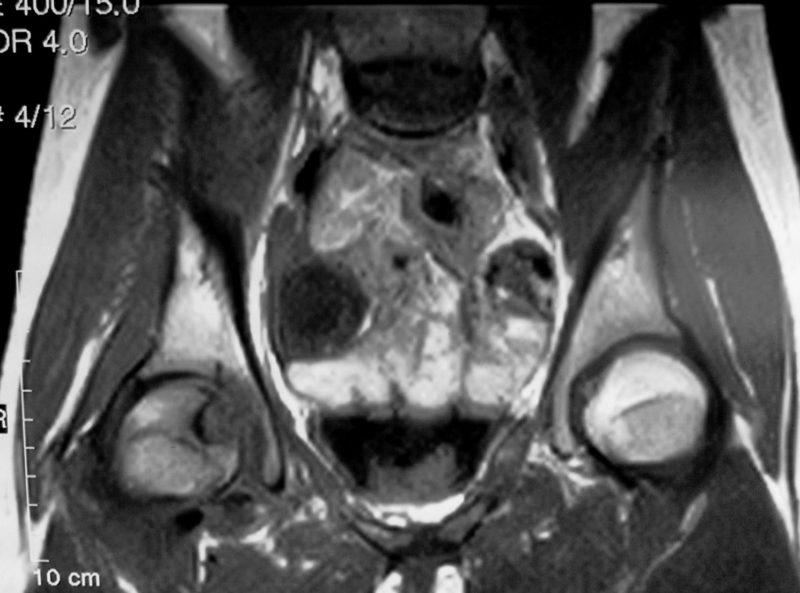

Снимки МРТ тазобедренного сустава показывают:

- наличие дисплазии;

- появление опухолевых образований в мягких тканях;

- повреждения сустава (микротрещины, разрывы, повышенная концентрация крови).

Фото МРТ тазобедренного сустава: